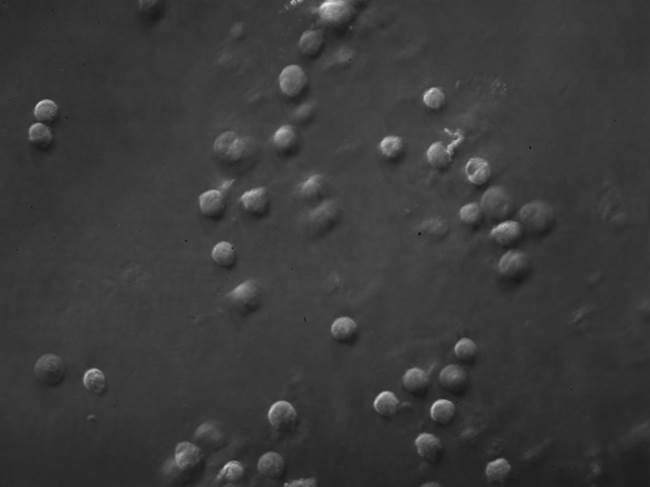

30 March 2015 Phase contrast microscopy ( living brain cancer cell ) Phase contrast microscopy living brain cancer cell Prev Next